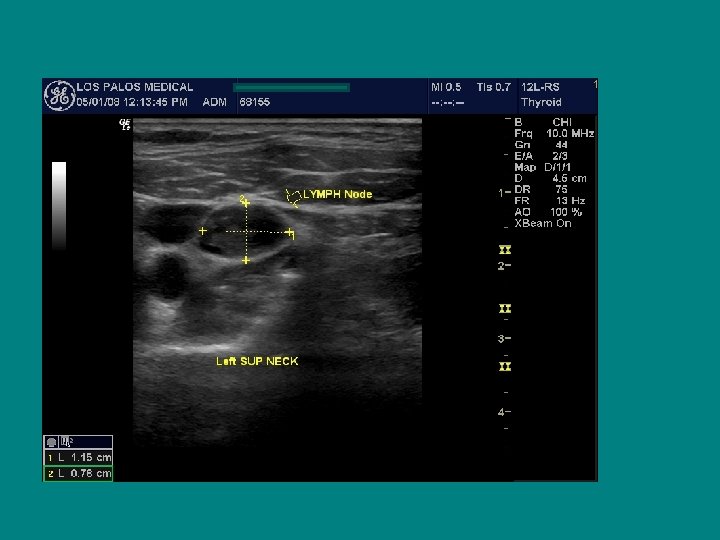

Ultrasonographic lymph node "map"

SEARCH FOR RECURRENT/RESIDUAL DISEASE • HYPOECHOIC MASS, LIKELY LYMPH NODE • AP/T 0. 7 CM !!

Ultrasound characteristics of a benign lymph node Ø Flattened or oval ( AP/T < 0. 5 Ø Echogenic Hilus Ø Hilar Flow on Doppler

Best ultrasound criteria for malignancy • Short to long axis diameter ratio of more than 0. 5 • It has 75 % sensitivity, 81 % specificity • 79 % accuracy

Does size help predict a malignant lymph node? • NO ! • Size doesn’t matter, • Border doesn’t help either

Cervical Ultrasonography, A. T. A recommends cervical ultrasound at 6 and 12 months after surgery and then annually